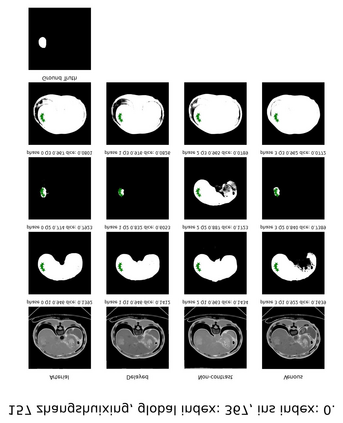

Learning to segmentation without large-scale samples is an inherent capability of human. Recently, Segment Anything Model (SAM) performs the significant zero-shot image segmentation, attracting considerable attention from the computer vision community. Here, we investigate the capability of SAM for medical image analysis, especially for multi-phase liver tumor segmentation (MPLiTS), in terms of prompts, data resolution, phases. Experimental results demonstrate that there might be a large gap between SAM and expected performance. Fortunately, the qualitative results show that SAM is a powerful annotation tool for the community of interactive medical image segmentation.